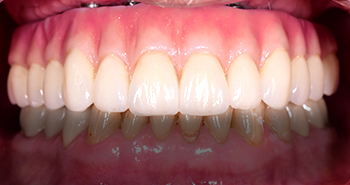

3.1 Fixed and Removable Implant Prosthetics

This prosthetic implant course covers full arch removable and fixed implant prosthodontics. The use and indications of fixed cement vs. screw in prostheses - their step by step manufacture and relative benefits are presented.

Indications and complications of cement vs. screw in prostheses

Understand the advantages and disadvantages of full arch fixed screw retained vs. cement retained prostheses

Appreciate the implant protective occlusal schemes for use in full arch fixed restorations